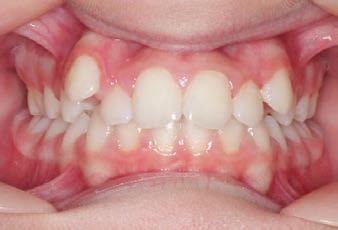

CLASS II DIV.1 - Marra

INITIAL - 4/4/18

PROGRESS 1 - 26/9/18 - Class I platform accomplished in 5.75 months with Motion 3D COLOR Appliance

PROGRESS 2 - 26/9/18 - Placement of the SLX 3D Clear Brackets